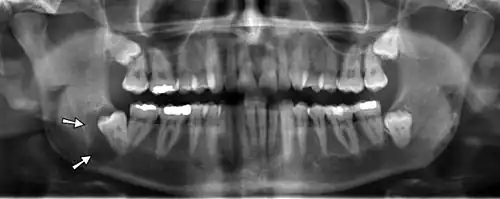

.jpg)

Panoramic radiographs have the capability to demonstrate a portion of the neck and display atheromas (calcifications in the carotid artery) which are an indication of both local and generalized (systemic) atherosclerosis. Atherosclerosis of the coronary arteries leading to myocardial infarction (heart attack), and atherosclerosis of the carotid artery leading to stroke are the number one and number three most common causes of death in the United States.[6]

There is interest to look at panoramic radiographs as a screening tool, however further data is needed with regards if it is able to make a meaningful difference in outcomes.[7]